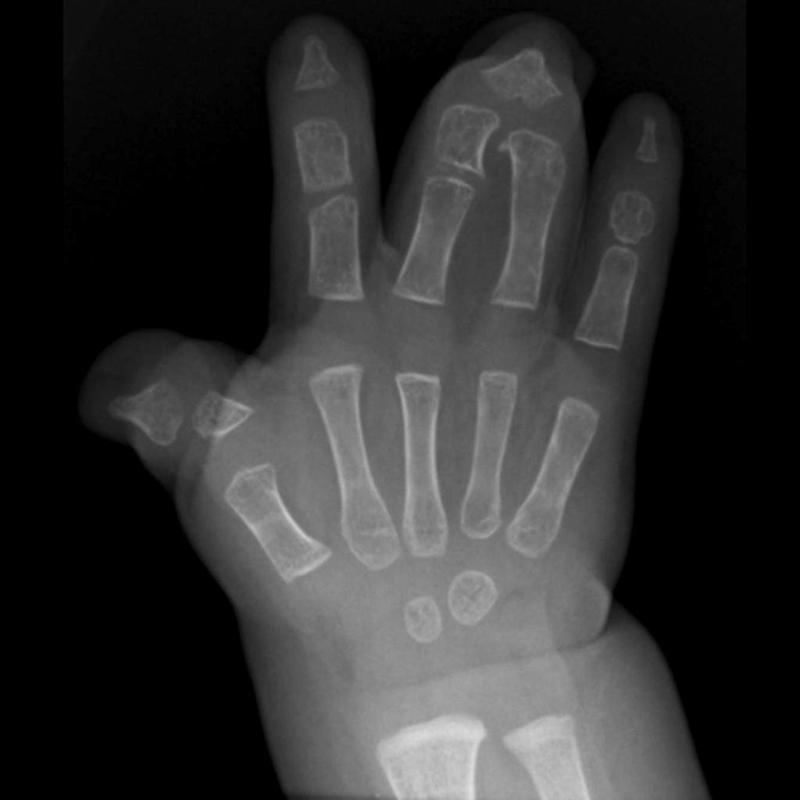

Для диагностики различных форм синдактилии применяются несколько методов исследования:

- рентгенография. Этот метод позволяет оценить состояние суставов и костных тканей. На рентгеновском снимке можно увидеть тип сращивания и степень спаечного процесса;